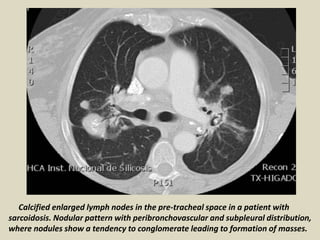

Calcified enlarged lymph nodes in the pre-tracheal space in a patient with

sarcoidosis. Nodular pattern with peribronchovascular and subpleural distribution,

where nodules show a tendency to conglomerate leading to formation of masses.